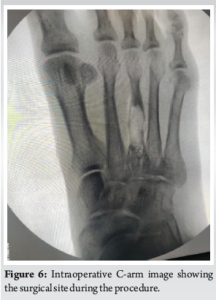

Case Report: We present a case of a 65-year-old male farmer who presented with swelling and persistent pain in the right foot, particularly over the third toe. The patient had a history of trivial trauma and previous incision and drainage for a foot swelling. Radiographic and magnetic resonance imaging findings indicated a well-defined lytic lesion with cortical thinning and breach over the third metatarsal, raising suspicion for tuberculous osteomyelitis. Surgical exploration revealed an encapsulated cyst filled with cheesy material. No sequestrated bone or osteomyelitis was found.

A 65-year-old male farmer presented to the outpatient department with complaints of swelling and persistent pain in the right foot, particularly over the third toe. The patient had been experiencing localized swelling and pain for the past 4–6 weeks, which did not subside despite treatment with antibiotics and analgesics prescribed by his local practitioner. The patient, a farmer by profession, lives with his spouse in a rural setting. His occupation, which involves significant physical activity, including walking, standing, and heavy lifting, likely contributed to the stress on his feet. He has no significant history of smoking or alcohol use. The patient reported a prior history of minor trauma to the right foot 5 years ago, which was managed conservatively with no long-term complications. Two years ago, the patient experienced similar swelling in the same foot, for which an incision and drainage procedure was performed at an outside hospital. Still, there were no subsequent issues after the procedure. At the time of presentation, the patient denied any systemic symptoms such as fever, weight loss, or malaise. He also reported no history of chronic conditions like diabetes, hypertension, or autoimmune disorders. The patient was not taking any long-term medications except for those prescribed for pain and swelling during the current episode. He had no prior history of significant illnesses or surgeries other than the previous minor trauma and surgical intervention on his right foot (Fig. 1-7).